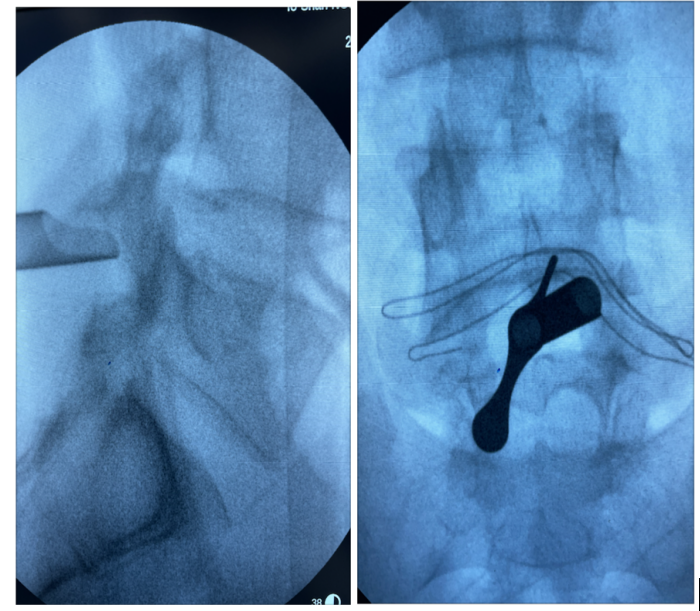

术中拍片定位突出位置

由于病情急迫,入院后第二天,就做了急诊手术:腰麻下施行微创经皮椎间孔镜下椎板间入路腰椎间盘髓核摘除术(PEID)